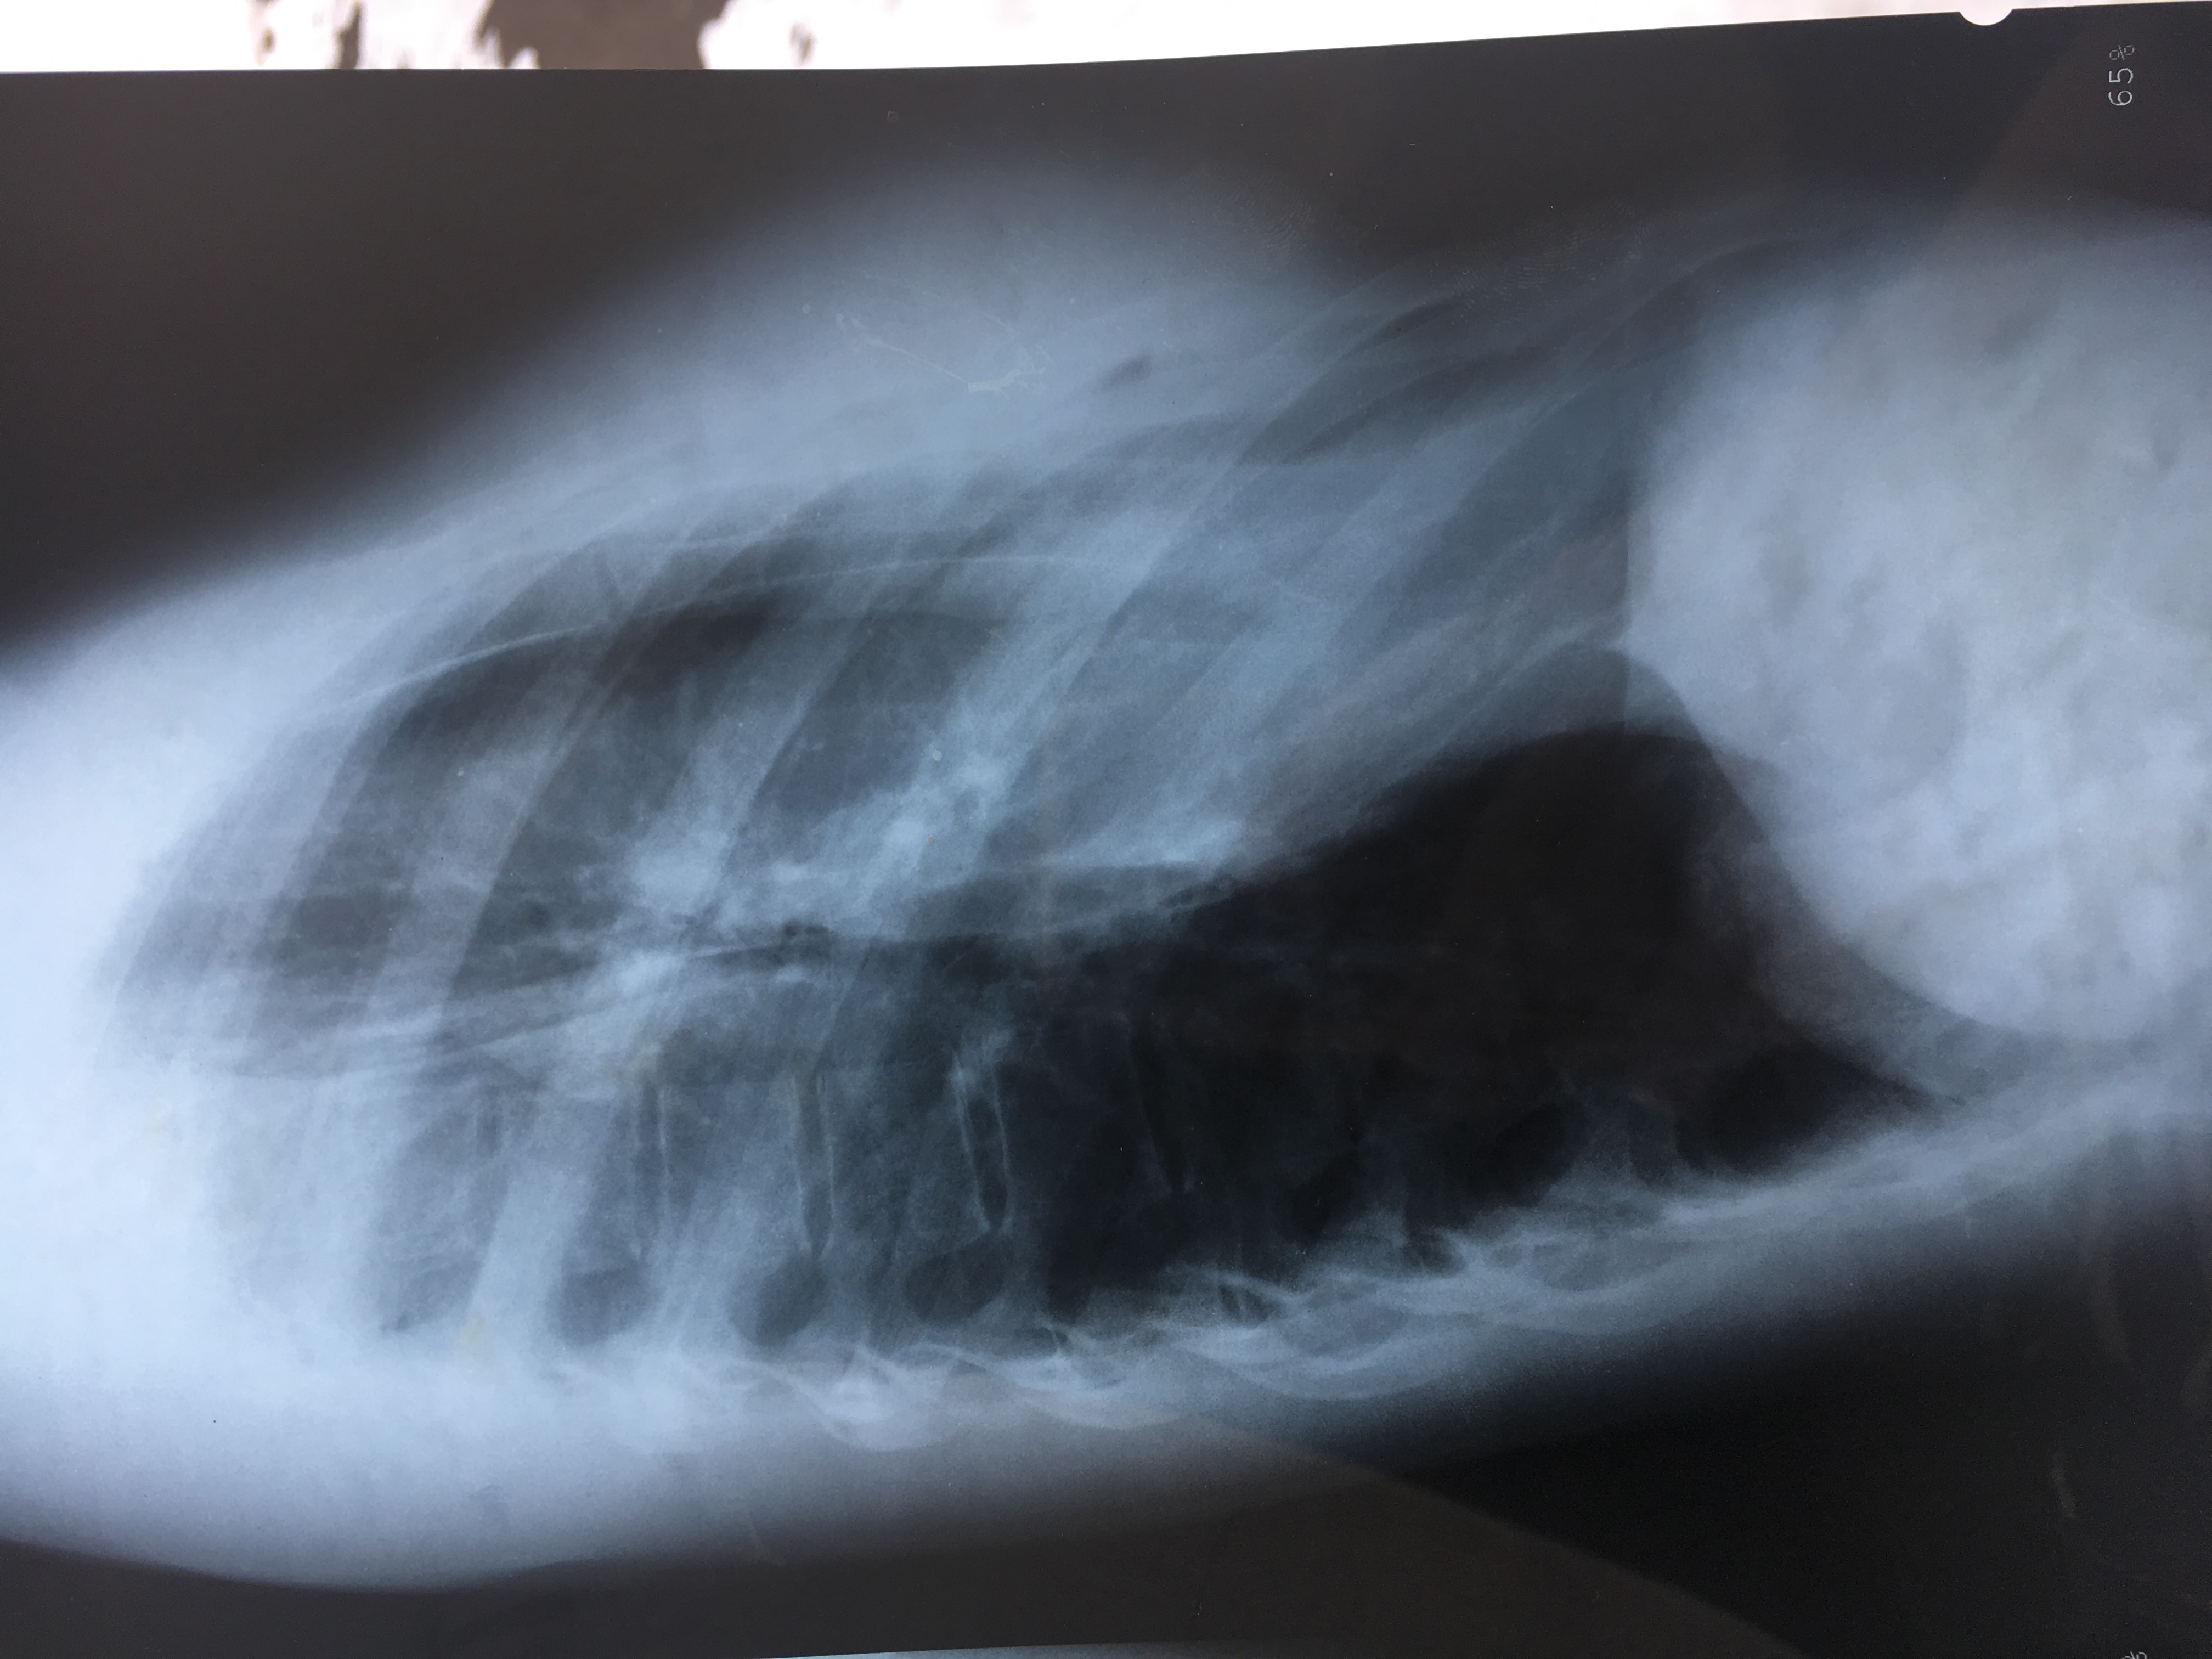

IMG_1581.JPG

Radio

Voilà une photo de mes radios, si ça suffit pas j'en ferais de moi..

Ben.. n'étant pas toubib, la radio ça ne dit pas grand chose.

Le mieux c'est une photo de 3/4 (pas de face, le creux ne se distingue pas)